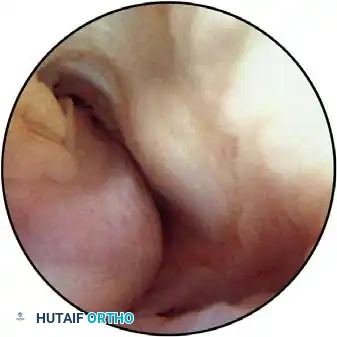

Portal Placement and Neurovascular Anatomy

Precise portal placement is the most critical aspect of elbow arthroscopy. A thorough understanding of the neurovascular anatomy is mandatory.

Joint Distention and Preparation

Before establishing any portal, the bony landmarks must be meticulously outlined with a marking pen:

* Lateral: Lateral epicondyle and radial head.

* Medial: Medial epicondyle and the course of the ulnar nerve.

* Posterior: Tip of the olecranon.

The joint must be maximally distended with 20 to 30 mL of sterile normal saline prior to portal placement. Distention pushes the anterior capsule—and the overlying neurovascular structures—anteriorly, significantly increasing the margin of safety.

Clinical Pearl: Fluid extravasation is the Achilles heel of elbow arthroscopy. Maintaining established portals with interchangeable cannulas (or cannulas with rubber diaphragms) is essential. This reduces the risk of damaging adjacent nerves with repeated instrument passage and decreases fluid extravasation, which can lead to devastating neurovascular compression (compartment syndrome) in the antecubital fossa.

Lateral Portals

The Direct Lateral Portal:

Located in the "lateral soft spot" where elbow effusions are most easily palpable and aspirated. It is situated in the center of the triangle formed by the lateral epicondyle, the radial head, and the tip of the olecranon. Instruments passed through this portal traverse the skin, subcutaneous tissue, anconeus muscle, and joint capsule. This is typically the first portal established to distend the joint.

Anterior Portals

The Anterolateral Portals:

Traditionally the standard diagnostic portal, the anterolateral portal is established after joint distention. There are three variations:

1. Distal Anterolateral: 2 to 3 cm distal and 1 cm anterior to the lateral epicondyle.

2. Midanterolateral: Just proximal and 1 cm anterior to the palpable radiocapitellar joint.

3. Proximal Anterolateral: 2 cm proximal and 1 cm anterior to the lateral epicondyle (described by Field et al.).

The anterolateral portal traverses the extensor carpi radialis brevis (ECRB) muscle and passes beneath the radial nerve.

Surgical Pitfall: The radial nerve is at extreme risk during anterolateral portal placement. Lynch et al. demonstrated that instruments may pass within 4 mm of the radial nerve in an undistended elbow. However, with 90 degrees of flexion and maximal joint distention, the distance increases to an average of 11 mm.

Field et al. found the safety margin is greatest with the proximal anterolateral portal (13.7 mm), followed by the midanterolateral (10.9 mm), and least with the distal anterolateral portal (7.2 mm).

Surgical Technique for Portal Entry:

Skin incisions must be made superficially with a No. 11 blade to protect the lateral and posterior antebrachial cutaneous nerves. A small hemostat is used to bluntly spread the soft tissues down to the capsule before a blunt trocar is introduced into the joint.